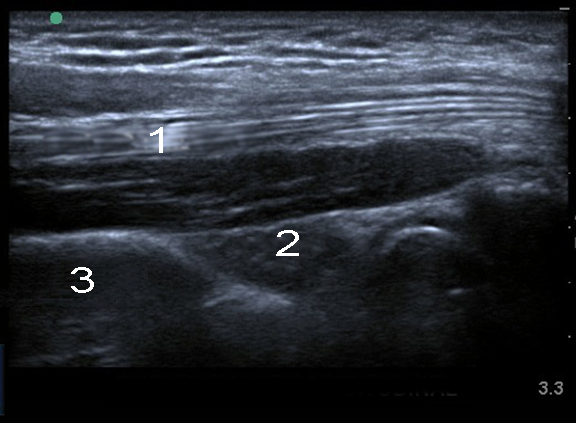

肘の上腕三頭筋腱の画像

三頭筋腱

脂肪層

上腕後部